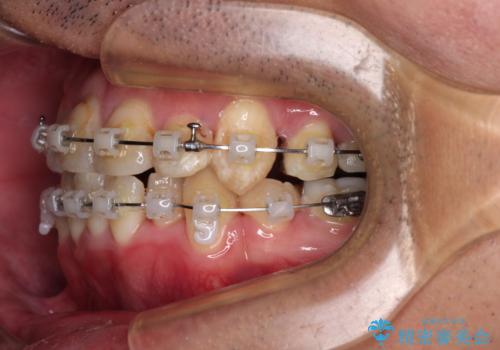

- 矯正装置

- クリアブラケット

- 治療期間

- 2年1ヶ月